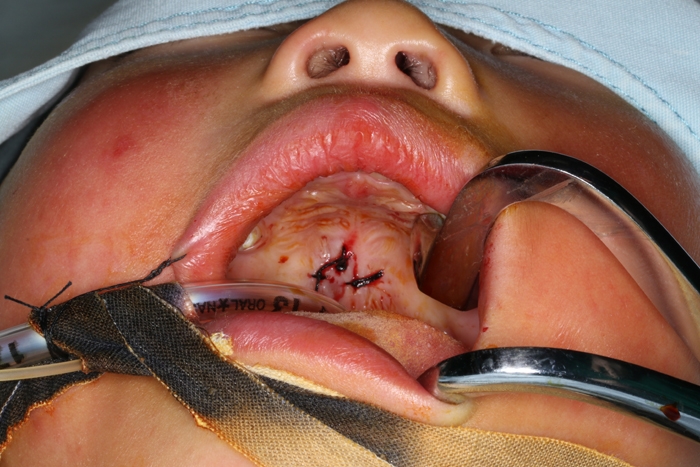

術(shù)后

取出的半截筷子

??? “慶幸的是,發(fā)生意外時,患兒手上拿的是竹筷子,比較脆,容易斷,如果當時拿在手上的是木頭筷子或者金屬制的尖銳物,那孩子當時倒地的一個沖擊力導(dǎo)致的可能就不是插在口腔上顎這么簡單了,可能會突破口腔,插入咽喉部或鼻腔內(nèi),再嚴重一些的插入顱腦也有可能?!毙灬t(yī)生介紹。